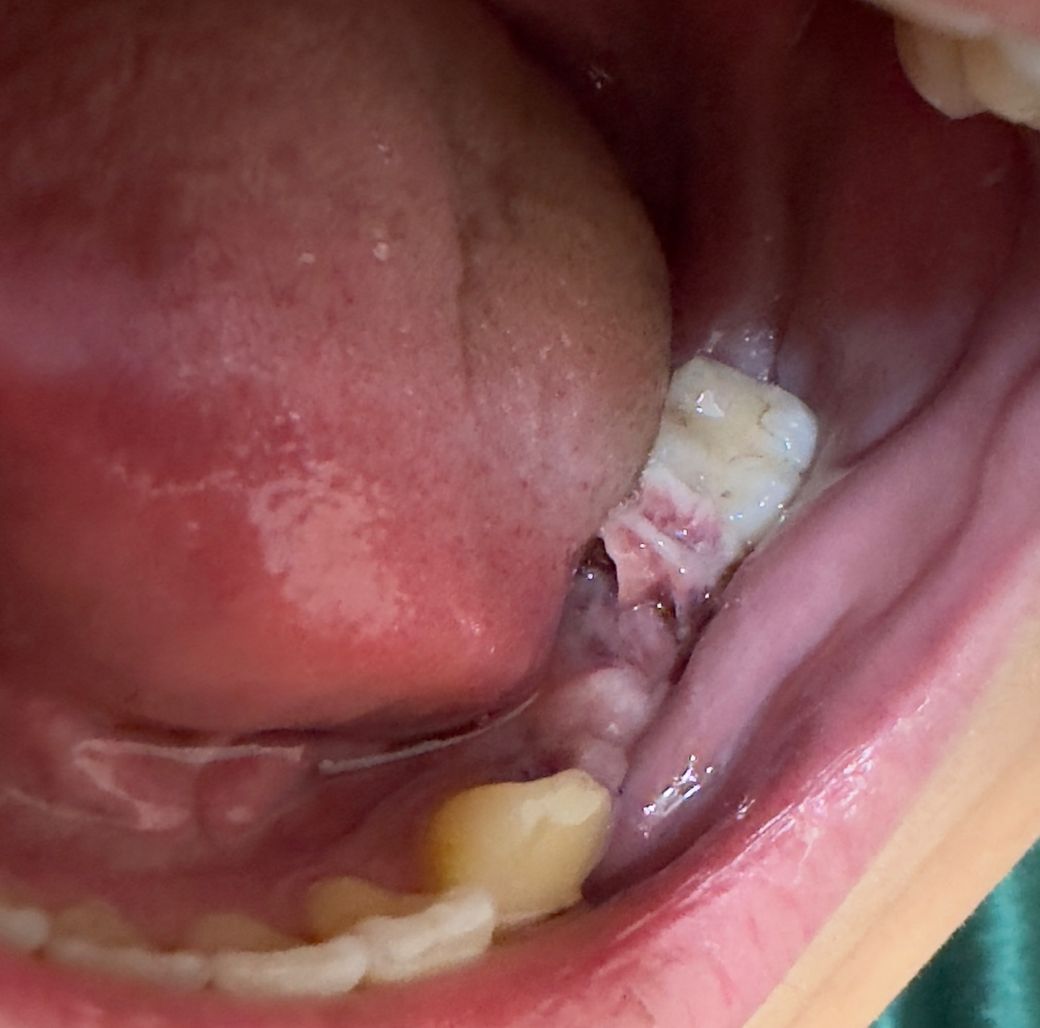

임플란트 및 뼈이식 후 잇몸 상태입니다

일주일 전 발치 후 5월3일에 치조골 이식 후 임플란트를 했습니다 총 3개를 하였고 윗 치아 1개 사진처럼 왼쪽 밑 치아 2개를 진행했습니다 피떡이 생기는건 알고 있었는데 윗 치아는 현재 아무런 고인 현상이 보이진 않고 사진에 보이는 2개의 수술 부위에는 저렇게 하얀 실 같은것들이 보입니다 일반적인 현상인지 궁금합니다 2주 뒤에 진료인데 괜찮을까요 통증은 없습니다

• 1번 째 사진

• 잇몸 수술을 하고 나서는 잇몸에 상처가 생길 수 있습니다. 이런 과정에서 가피 등의 형성이 되어 하얀색 띠를 보이는 경우도 있습니다. 잇몸 수술을 했다면 해당 부위를 자극하지 않는 것이 좋습니다

• 현재 사진상으로특별히 문제가 없고 잘 아물고 있는 것으로 보입니다. 염증이 덧나지 않도록 2주간은 흡연 및 음주는 피하고, 소독용 가글로 가글하여 관리하길 권합니다.

• 염증의 양상은 보이지 않으나 상처가 나서 그런 것으로 보입니다. 혹시 통증이 느껴지거나 더 붓는다면 치과를 가보시는 게 좋겠습니다.

• 안녕하세요 치과의사 김철진입니다. 뼈이식을 하고 차폐막을 씌워 놓은게 아닐까 생각됩니다. 잇몸이 5일만에 저렇게 과증식 되진 않앗을꺼같으니 그래도 혹시 모르니 치과에 가셔서 체크를 한번 받아보세요.